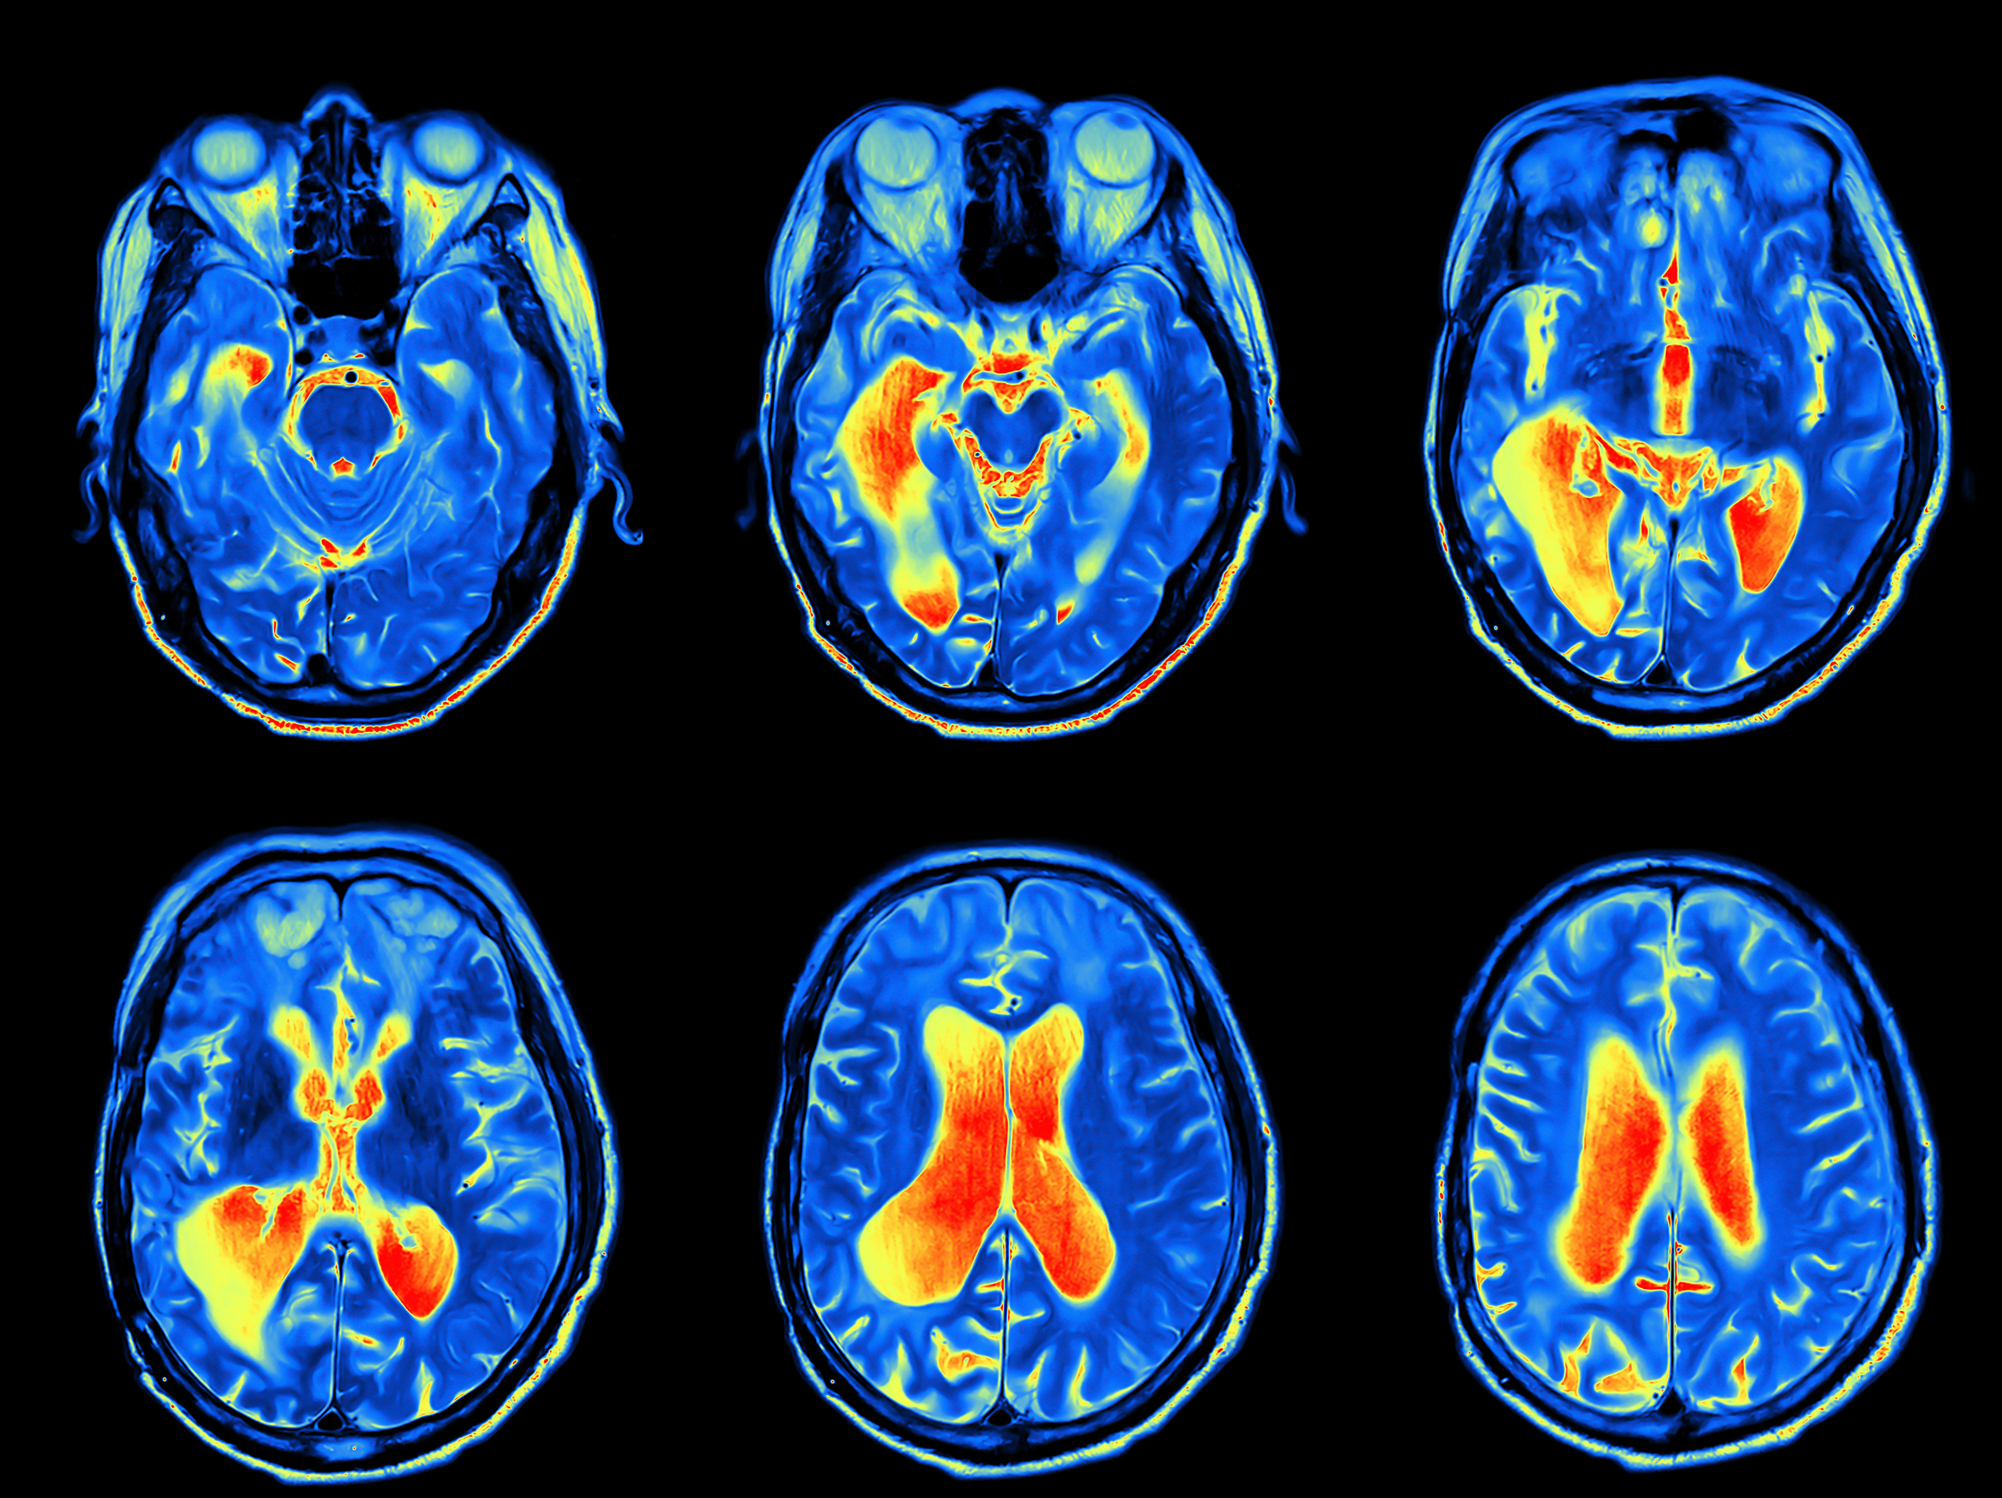

mri-scans-brain

Associate Professor Sarah Spencer is a leading researcher in the Neurodevelopment in Health and Disease group at RMIT, looking at stress and perinatal programming of disease. Her work brings together stress, neuroinflammation, and developmental physiology with a focus on investigating the effects of early life dietary manipulations on the stress and metabolism in the adult animal.

"Neuroimmunology of the female brain across the lifespan: plasticity to psychopathology" (DOI 10.1016/j.bbi.2019.03.010) is published in Brain, Behavior, and Immunity.